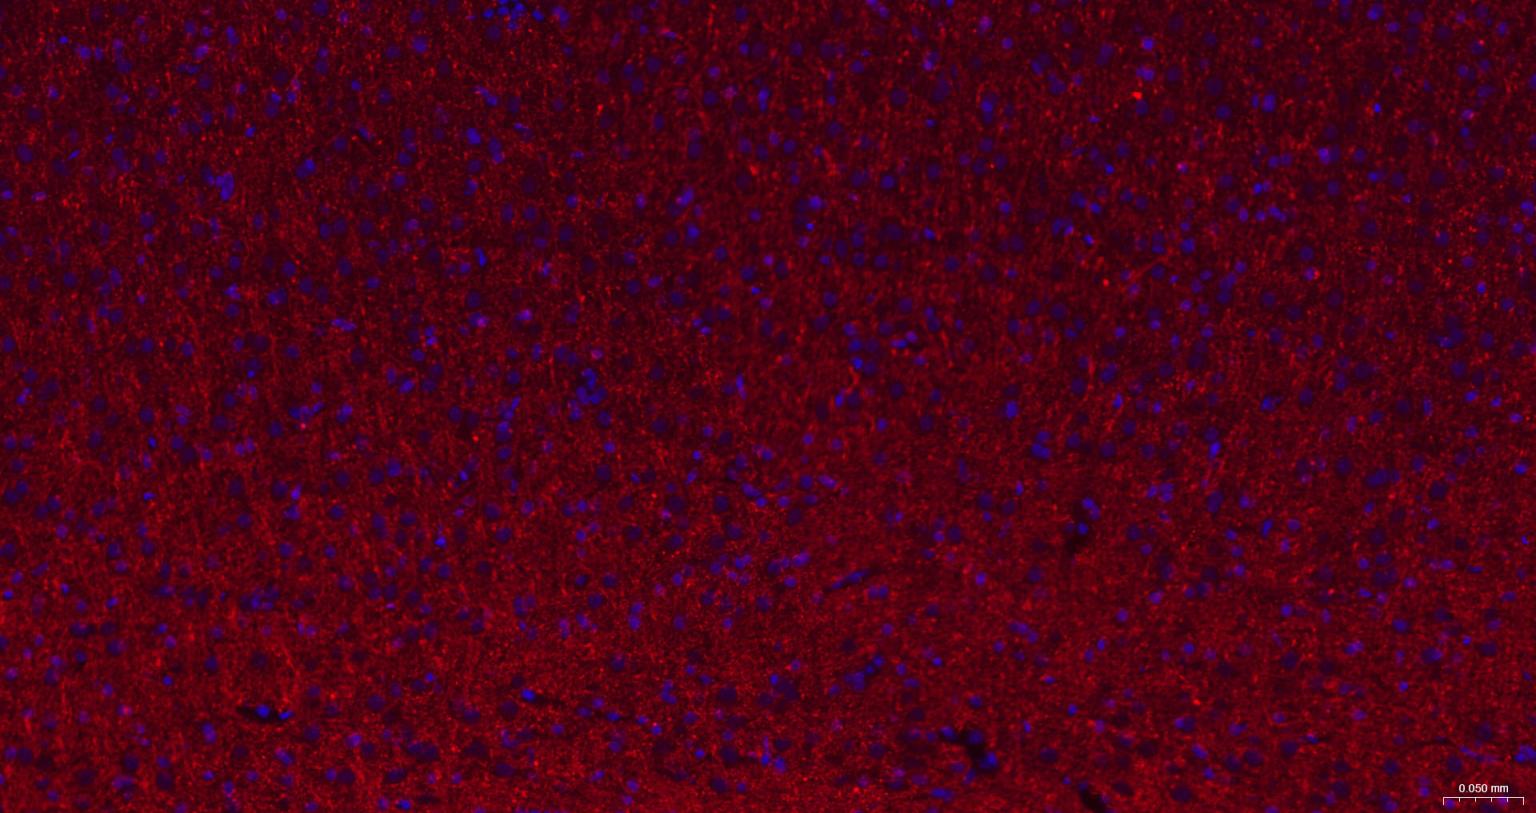

Paraformaldehyde-fixed, paraffin embedded Human Cerebrum; Antigen retrieval by boiling in sodium citrate buffer (pH6.0) for 15 min; The section was incubated with CNPase Monoclonal Antibody, Unconjugated (bsm-61411R) at 1:200 overnight at 4°C. Followed by conjugated Goat Anti-Rabbit IgG antibody (Red, bs-0295G-BF594), DAPI (blue, C02-04002) was used to stain the cell nuclei.